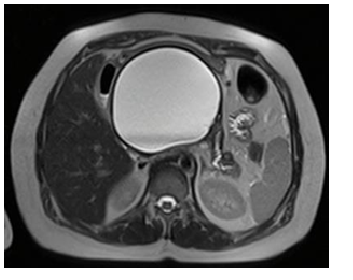

A 72-year-old female patient with a history of acute biliary pancreatitis, arterial hypertension, type 2 diabetes mellitus, and cholecystectomy. She presents 10 years after pancreatitis with 1 year of abdominal pain. Physical examination: evident protrusion and painful palpation in the left upper abdominal quadrant. Normal laboratory results. Contrast-enhanced CT and MRI showed an 11 x 9 cm pseudocyst. It was punctured with a 19G needle and two 9 cm x 7F double Pigtail stents were placed (Figures 3 & 4). After 6 months of follow-up, only residual inflammation was evident and the stents were subsequently removed. Favorable clinical outcomes (Figures 5 & 6).

Figure 5 Contrast-enhanced CT: (15 days after drainage). Dimensions decrease of the pseudocyst (asterisk). With hidroaereos level in this one with stent in situ.

Figure 6 Contrast-enhanced CT: (15 days after drainage). 2 double Pigtail stents in situ between stomach (arrowhead) and the pseudocyst (arrows).